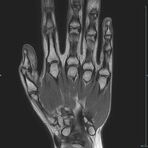

Gelenke

Hand

• Beurteilung von Knochen, Bändern und anderen Weichteilstrukturen der Gelenke nach Unfall.

• Arthrosediagnostik (Knorpelschaden)

• Impingement-Symptomatik

• Ursachenklärung bei wiederholter spontaner Gelenkluxation

• Ausbreitungsdiagnostik bei Gelenkentzündung, z.B. im Rahmen von rheumatischen Grunderkrankungen